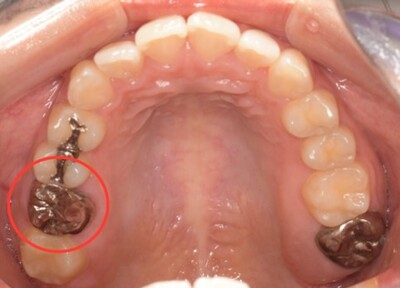

移植12ヶ月後の口腔内写真

移植12ヶ月後のレントゲン

移植12ヶ月後。セラミッククラウンで歯冠を修復した。

デンタルX線写真では透過像もほぼ消失している。